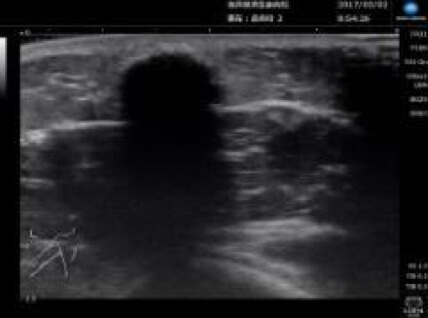

超音波診断装置

超音波を用いた皮下腫瘍の診断や、外傷時の皮下異物などの診断に役立ちます。視診、触診だけではわからない情報をたくさん得ることができます。患者さんは痛みもありませんので、子供さんでも検査を受けることができます。

コニカミノルタの超音波機器を導入しています。